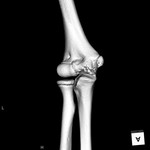

[画像診断]小児の肘、骨化核出現時期について、3D-CT(VR表示) 2011-04-27